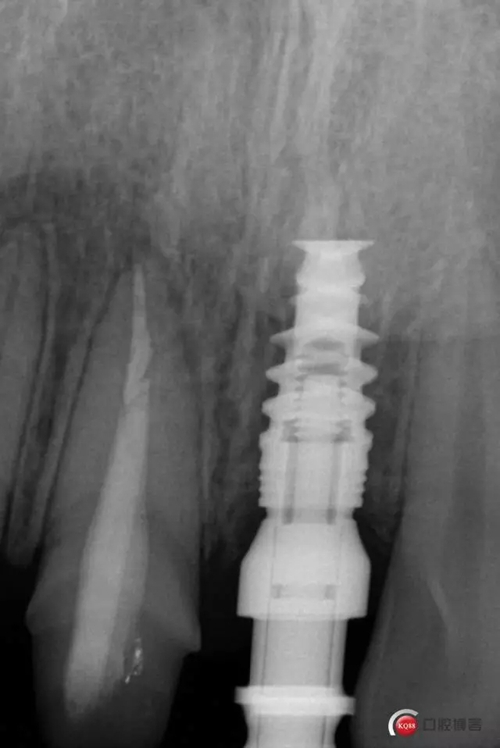

種植后修復(fù),我們要把握每一個細(xì)節(jié),比色,轉(zhuǎn)移桿的就位,我們必須把臨床做好,技工師傅才會給我們做出好的修復(fù)體,減少一些不必要的失誤,首先術(shù)前的檢查是必要一步 ,再是器械的準(zhǔn)備使我們臨床操作有條不紊,術(shù)前拍照,o-bite取咬合記錄,消毒修復(fù)術(shù)區(qū),旋出愈合基臺,生理鹽水沖洗袖口,拍照袖口,安放合適轉(zhuǎn)移桿,拍X線見轉(zhuǎn)移桿就為良好,硅橡膠取模,術(shù)后旋回愈合基臺,拍照比色。